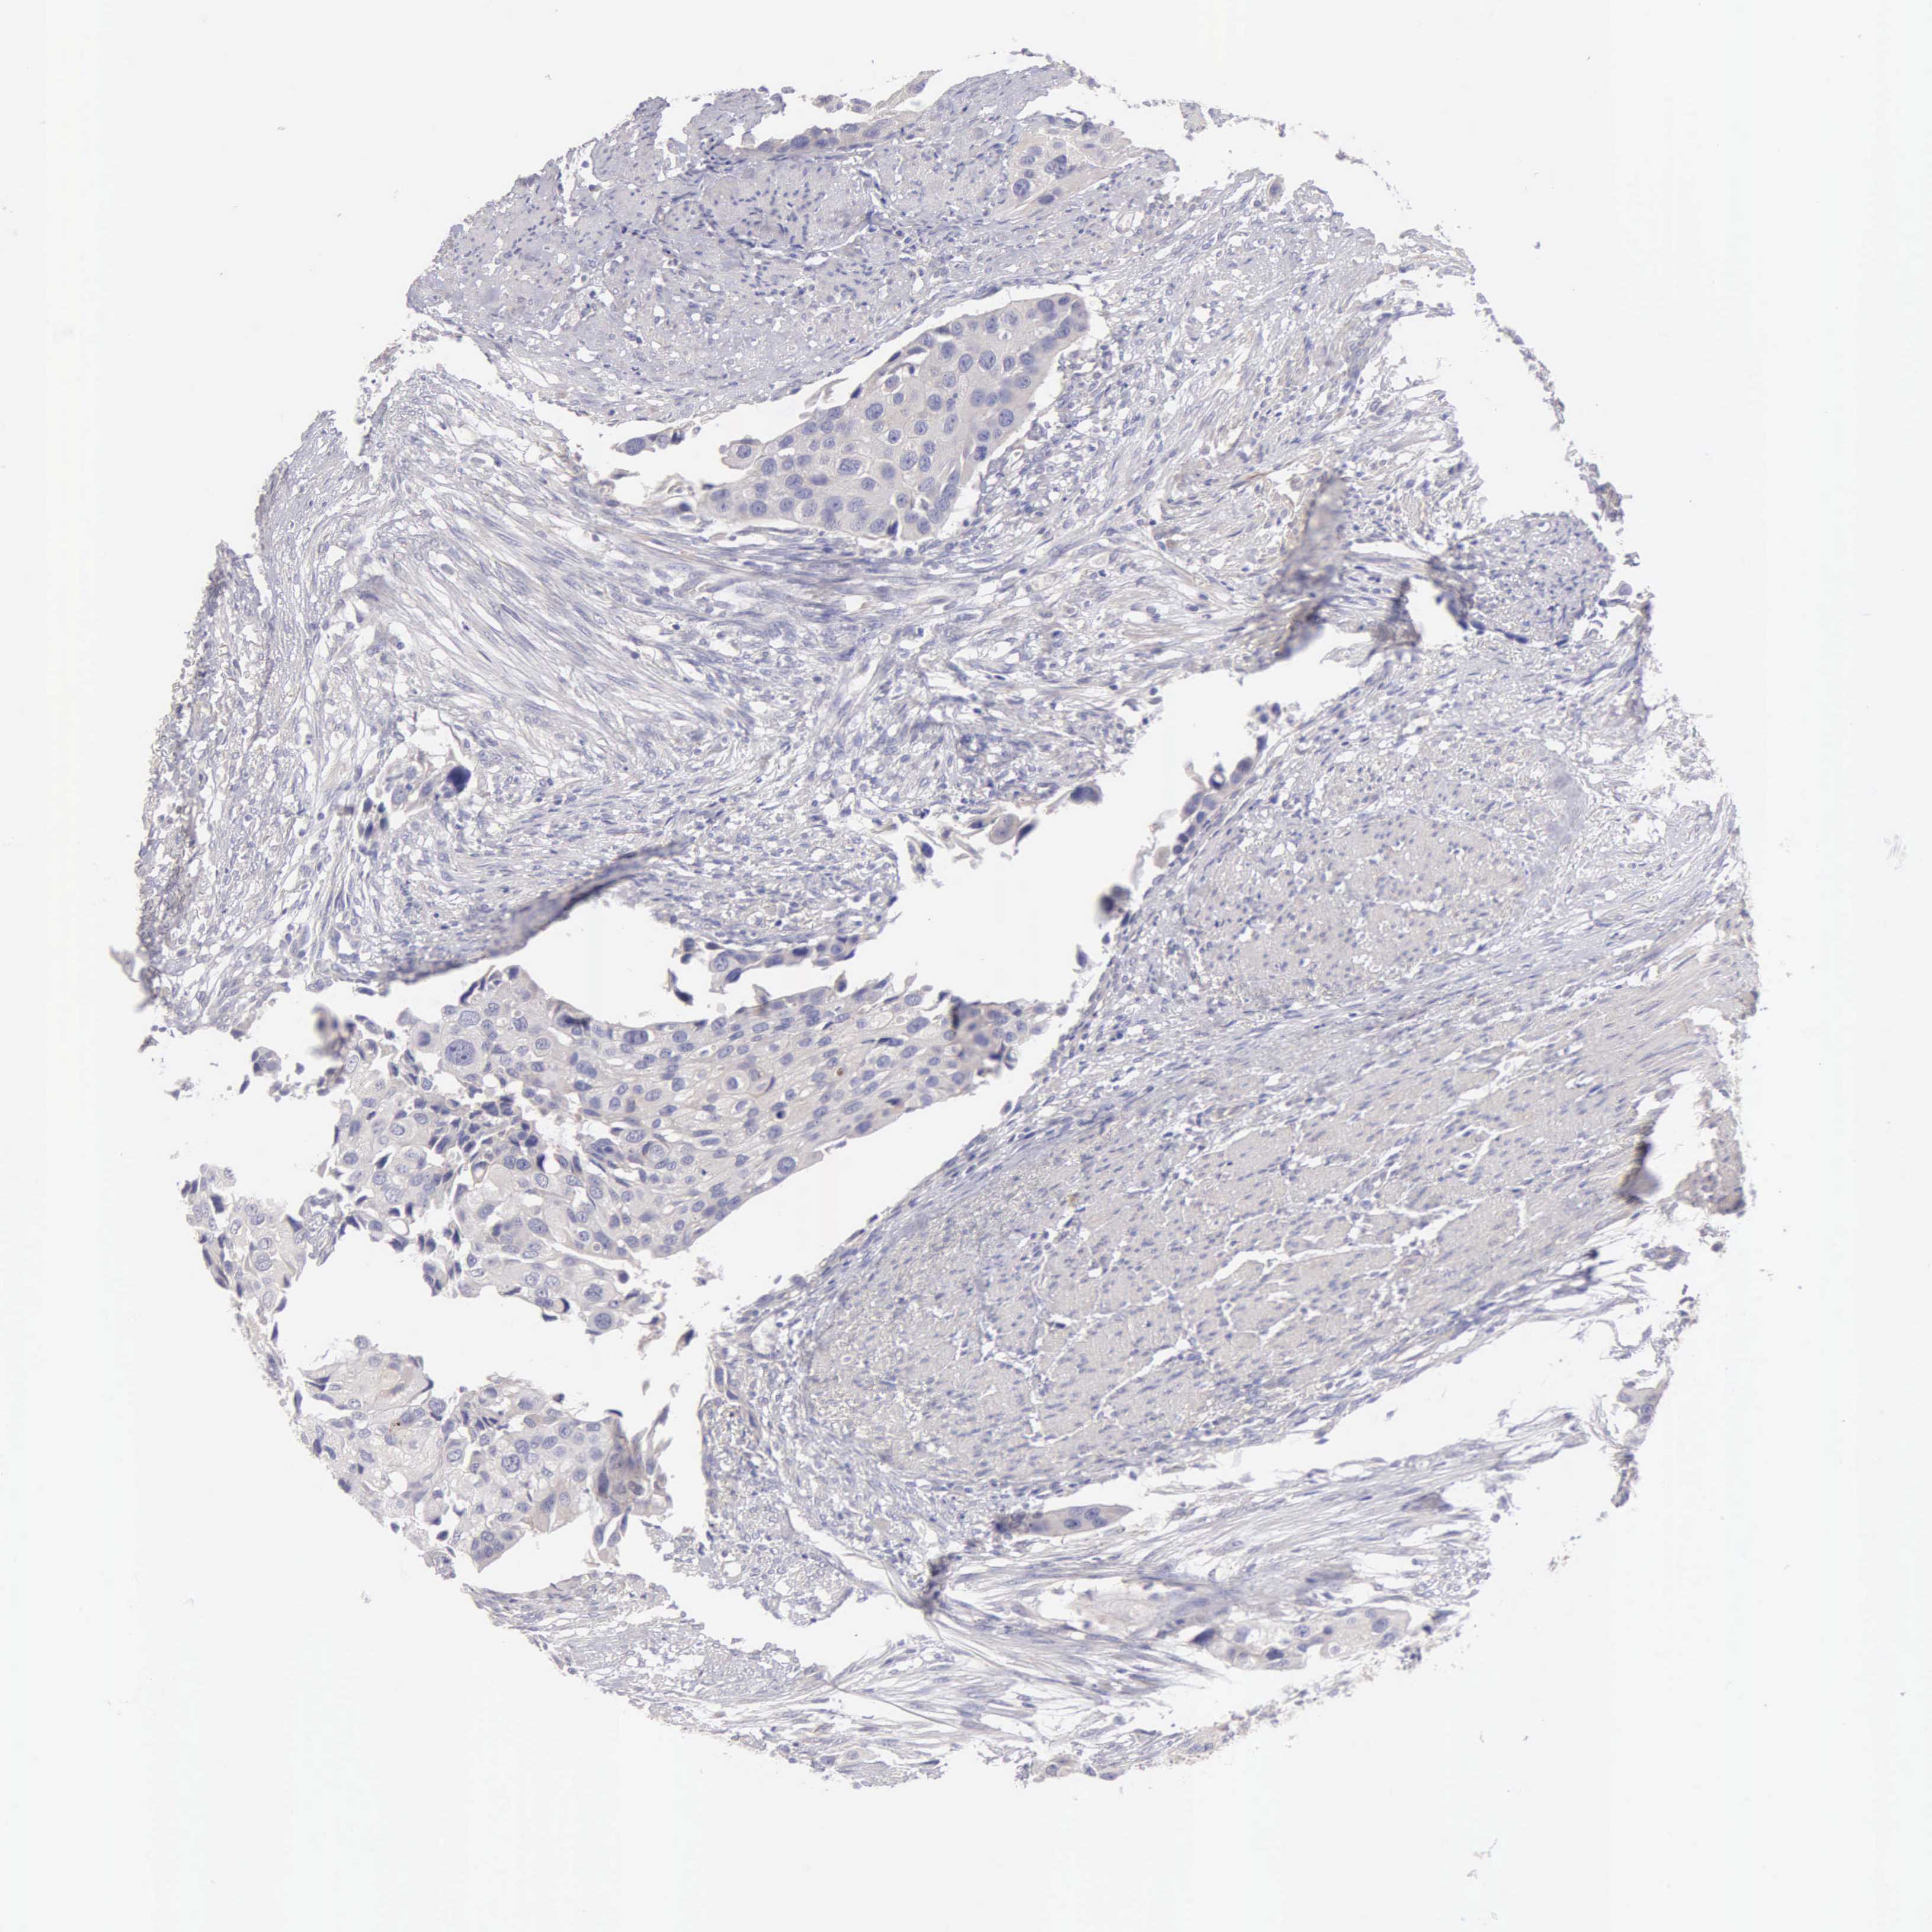

UROTHELIAL CANCER - Protein expressioni

A mouse-over function shows sample information and annotation data. Click on an image to view it in a full screen mode. Samples can be filtered based on level of antibody staining by selecting one or several of the following categories: high, medium, low and not detected. The assay and annotation is described here.

Note that samples used for immunohistochemistry by the Human Protein Atlas do not correspond to samples in the TCGA dataset.

Antibody stainingi

Antibody staining in the annotated cell types in the current human tissue is reported as not detected, low, medium, or high, based on conventional immunohistochemistry profiling in selected tissues. This score is based on the combination of the staining intensity and fraction of stained cells.

Each image is clickable and will lead to virtual microscopy that enables deeper exploration of all samples and also displays staining intensity scores, fraction scores and subcellular localization as well as patient and tissue information for each sample.

Antibody HPA001462

Antibody CAB000157

Urothelial carcinoma, High grade

Urothelial carcinoma, Low grade

Adenocarcinoma, NOS